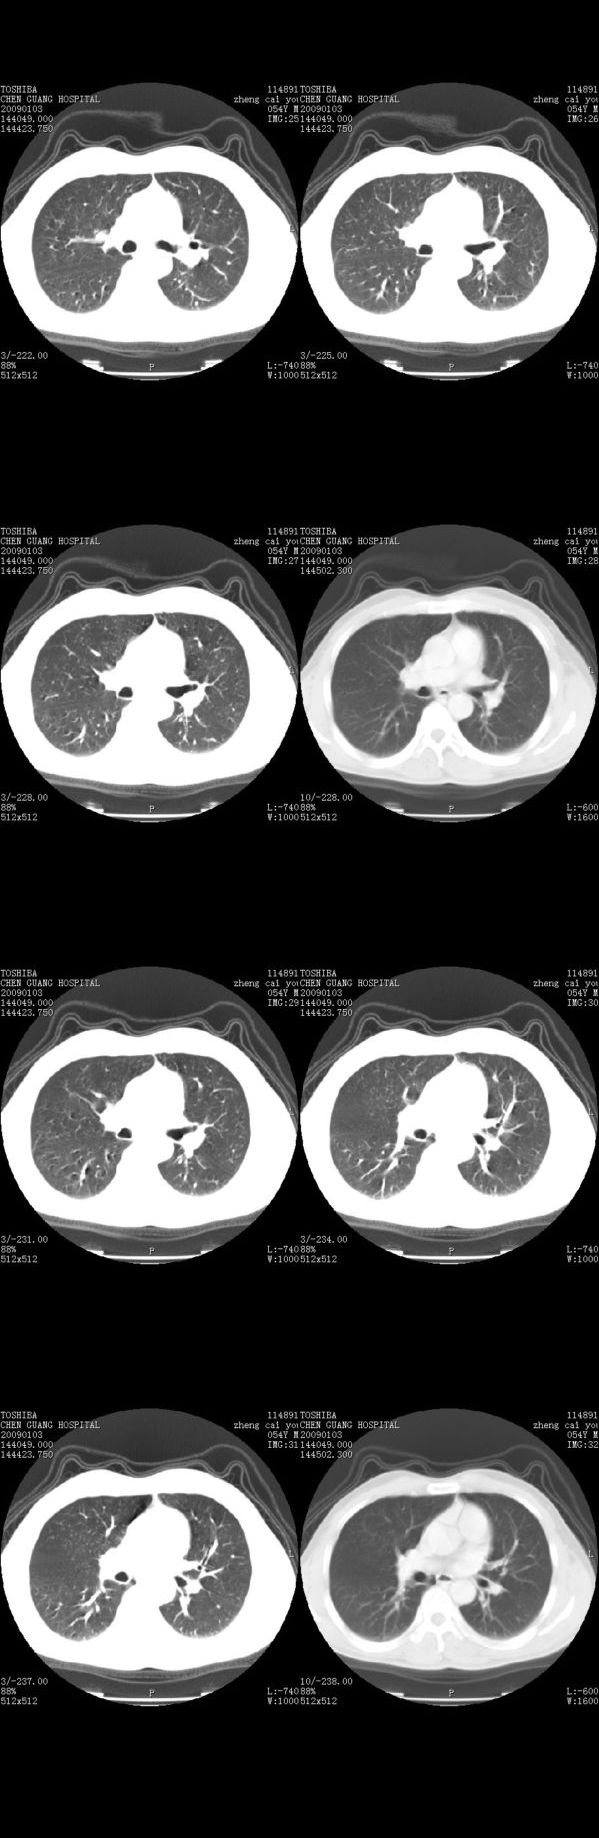

男,54岁,平时有吸烟后咳嗽、咯痰史,因右侧胸部(腋窝下)疼痛来检查平片,见右下肺动脉干起始处处结节,后到同学处做了平扫及增强。请各位老师帮忙看一下,不甚感谢!!!!!

顺序确实有点乱,不过在右肺上叶后段近气管旁仍可见一结节灶,希望楼主小心观察分析。

肺窗薄扫、常规扫描均未见明确病变;右下肺门圆形与肺血管等密度影,考虑为血管变异;应该要纵隔窗才能进一步明辨。

右肺上叶前后段支气管夹角处可见一结节影,图像资料不全,不好下结论。